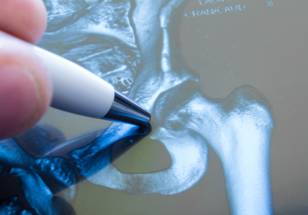

For patients undergoing total hip arthroplasty (THA), the use of robotic-assisted surgery and surgical navigation techniques is not associated with an increased risk of periprosthetic joint infection (PJI), suggests a study in The Journal of Bone & Joint Surgery. The research was led by Alberto V. Carli, MD, and colleagues of Hospital for Special Surgery, New York.

Computer navigation and robotic assistance are increasingly used during THA. These technologies have shown beneficial effects, including more accurate component positioning and a lower risk of postoperative instability. However, "It remains unknown as to whether use of [CN and RA] leads to an improvement in long-term functional outcomes or implant longevity," according to the authors.

The use of CN and RA requires the presence of additional equipment and personnel in the operating room, and has been linked to longer operating times. Together, these factors might lead to an increased risk of surgical-site contamination and PJI, a major cause of implant failure after THA.